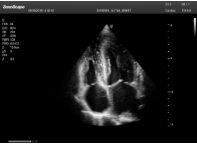

2相控陣探頭

探頭面是平面,接觸面小,近場視野最小,遠場視野大,成像視野呈扇形,適用于心臟。

心臟探頭通常按應(yīng)用人群劃分為成人、兒童、新生兒三類:(1)成人心臟位置最深、搏動速度慢;(2)新生兒心臟位置較淺、搏動速度最快;(3)兒童心臟的情況介于新生兒與成人之間。

肥厚性心肌病-心尖四腔